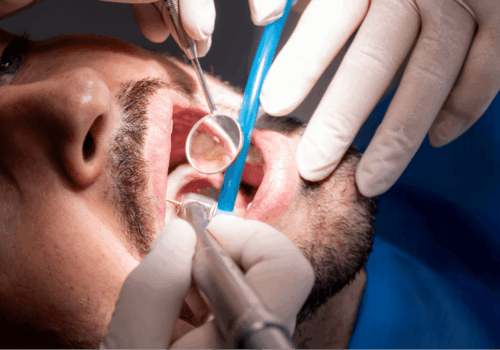

L’intervento si realizza grazie all’inserimento di radici artificiali in titanio (impianti dentali),

mediante le quali è possibile apportare diverse soluzioni nella bocca del paziente: